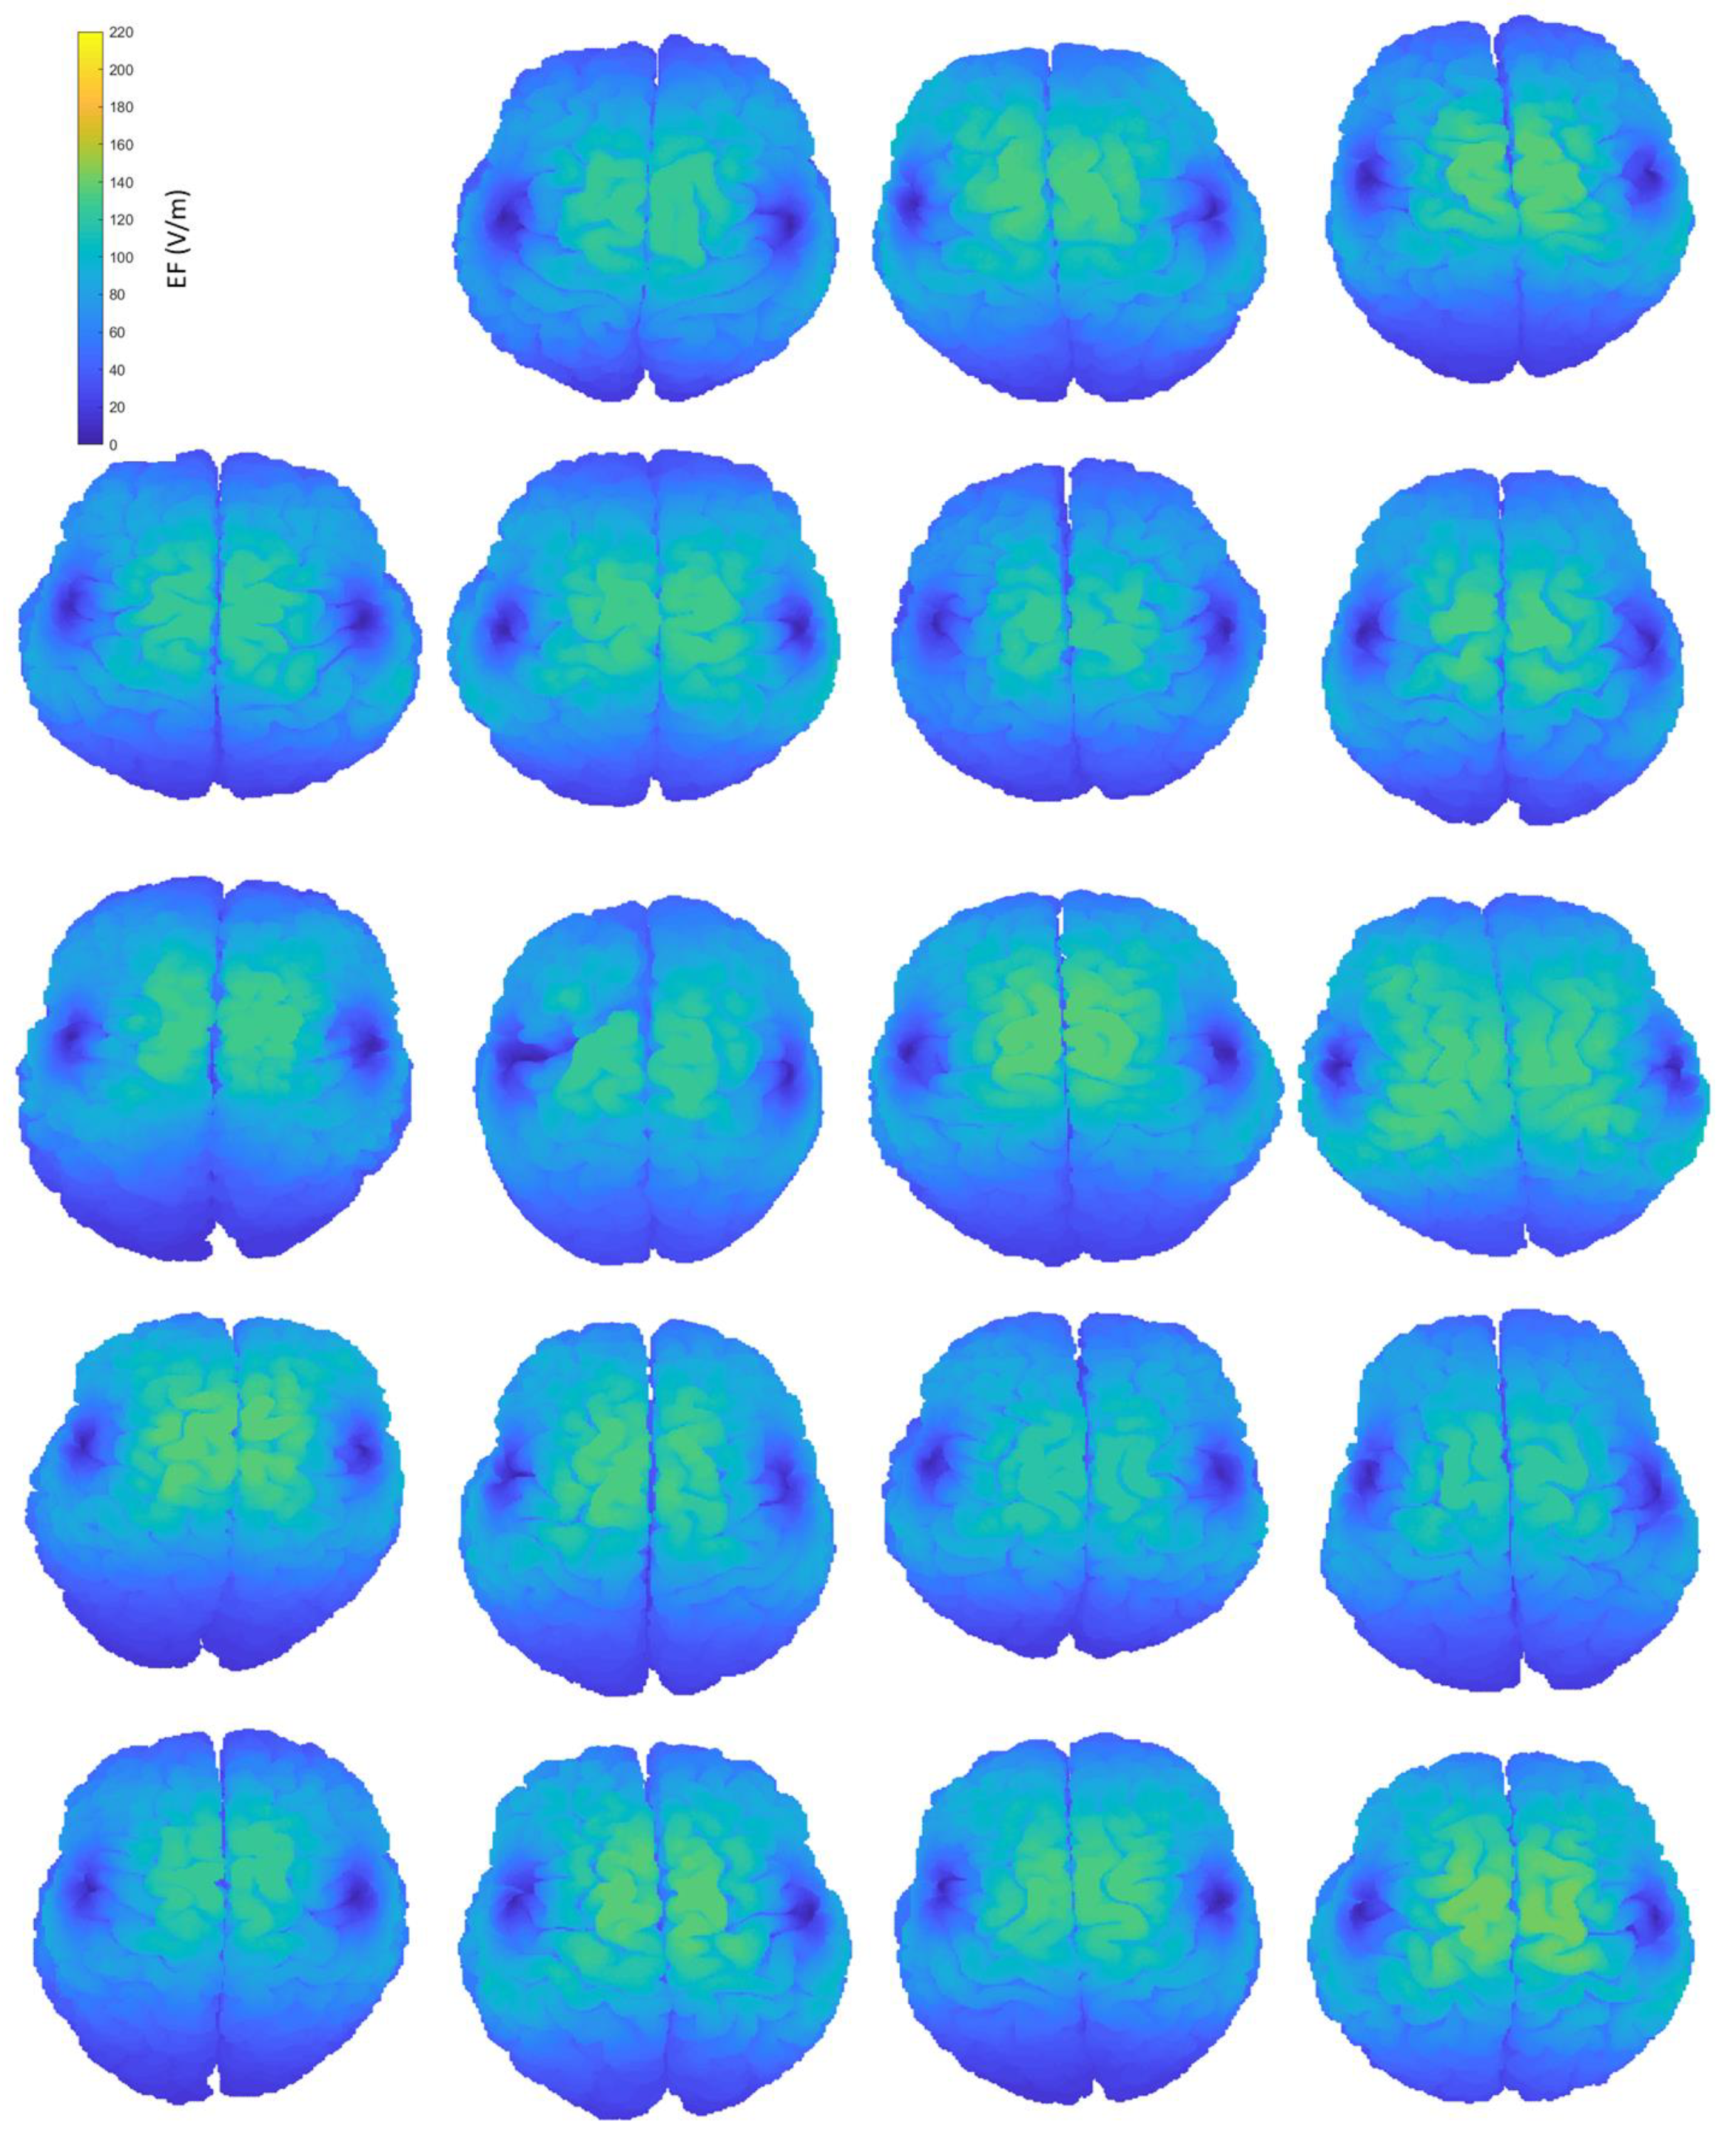

Figure A1.

Interindividual variability of the induced EF distributions visualized on subjects’ anatomical brains, containing both grey and white matter, when the coil is placed at frontal position.

Figure A2.

Interindividual variability of the induced EF distributions visualized on subjects’ homogeneous brains, containing both grey and white matter, when the coil is placed at frontal position.

Figure A3.

Interindividual variability of the induced EF distributions visualized on subjects’ homogeneous brains, containing both grey and white matter, when the coil is placed at central position.